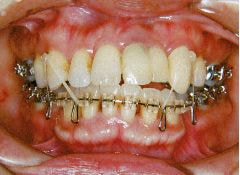

治療例1 (インプラント補綴+矯正)